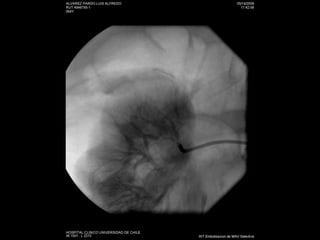

Nefrostomías  Éxito cercano a un 100% Complicaciones 4% hemorragia-infección Inserción anterógrada de catéter doble J

Nefrostomías Éxitocercano a un 100% Complicaciones 4% hemorragia-infección Inserción anterógrada de catéter doble J